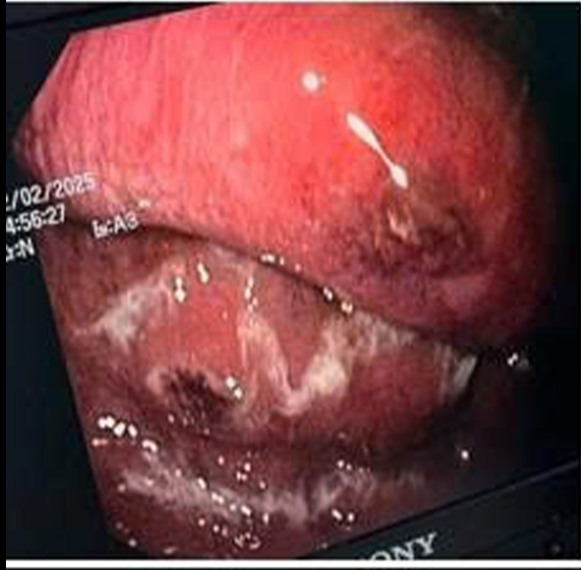

中央軍事病院 108 の医師たちは、壊死性ガス発生性胃炎という極めて稀な病気に苦しむ 68 歳の患者の命を救ったところです。